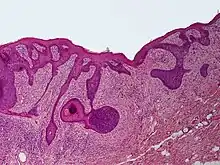

Perifollicular fibroma is a cutaneous condition, a benign tumor usually skin colored, most often affecting the face and upper trunk.[1]: 674 [2]